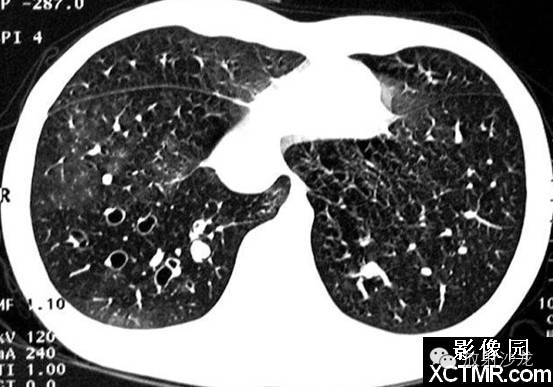

印戒征见于胸部CT扫描。它是由一小圆形软组织密度影邻接一围绕大圆形低密度空气影的环状软组织密度影构成。

在横断面CT扫描上,环状软组织密度影代表扩张的支气管壁,圆形低密度空气影代表扩张的支气管内气体。与环邻接的圆形软组织密度影代表与扩张支气管伴行的肺动脉的横断面影像。

支气管扩张的胸部平片表现包括扩张的充气支气管,支气管壁增厚,肺实质体积减小,支气管聚集。也能见到由于肺炎或纤维化所致的肺透亮度异常。在薄层CT可见到支气管扩张,缺乏支气管尖端变细,在胸膜1cm内见到支气管,支气管壁增厚和印戒征等。支气管与动脉比率随不同参数而变化,例如CT扫描的海拔高度,因此,仅发现支气管直径大于相邻动脉不足以诊断支气管扩张。

2.CT表现 ①HRCT可见支气管壁增厚,管腔增宽,距胸膜下3cm的肺周边部也见到支气管;②可见“轨道征”和“印戒征”,扩张的支气管管径大于伴行的肺动脉直径,此时如支气管的走行方向与CT扫描平面垂直,即构成特征性的“印戒征”;如支气管走行与CT扫描平行时,表现为“轨道征”;③扩张的支气管内为黏液所充盈时,表现与血管伴行而粗于血管的柱状或结节状高密度影;④曲张型支气管扩张管壁不规则,可呈串珠状;囊状支气管扩张则表现为一组或多发性含气的囊肿,若囊内充满液体则呈现一串葡萄状,囊内出现气液平面是囊状支气管扩张最具特异性的征象